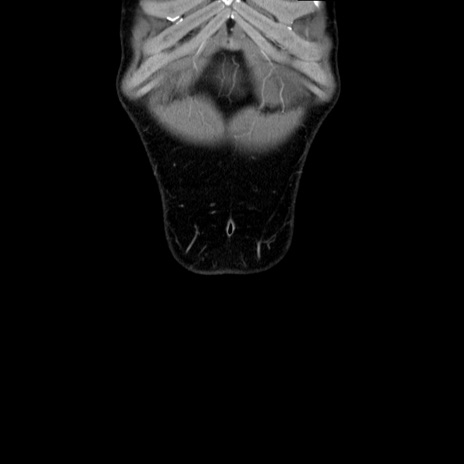

症例36(冠状断像)

【症例】20歳代 男性

【主訴】心窩部痛

【現病歴】今朝より上腹部痛あり。一旦軽快していたが再度出現したため救急要請。昨日夕に白身の魚を含む刺身を食べた。

【身体所見】BP 136/89mmHg、HR 74/min、BT 37.0℃、腹部:膨満、軟、心窩部に圧痛あり。反跳痛なし、筋性防御なし、腸雑音やや亢進あり。

【データ】WBC 17700、CRP 0.48